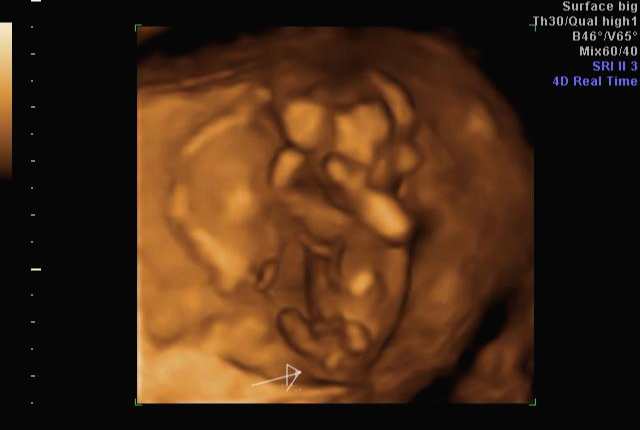

입체 초음파 사진은 항상 만족스러워요! 사진 보면 벌써 태어난 아기처럼 어찌 이리 이목구비 뚜렷하고 아이 얼굴이 선명하게 잘 보이는지~ 제아이라 이렇게 사랑스러운 걸까요~? ㅋㅋㅋ

내 뱃속에 이렇게 사랑스러운 아이가 있다니 >. < 이렇게 이쁜 아이를 보면 성별반전은 중요하지 않아요~